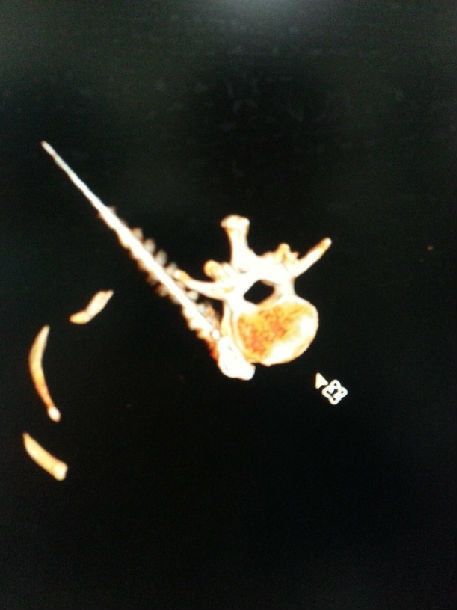

腰交感神经化学毁损术是一项通过使用医用酒精毁损部分腰交感神经组织,从而阻断其神经传导功能的微创介入治疗手段。手术在CT引导下,使用一根直径仅0.7mm的穿刺针,到达L2椎体前外侧的交感神经节处,注射造影剂,显示位置确切后,注射75%医用酒精15ml对腰交感神经进行毁损,通过损毁部分交感神经节后纤维,使交感神经兴奋性降低,不仅增加腰部动、静脉的血流量,使神经根缺血得到改善,还使其支配的下肢血管扩张,侧支循环建立,使下肢整体的血液循环得到改善,从而治疗因腰部及下肢缺血而引起的疾病。手术效果确切,起效快,时间短,无不良反应及后遗症,术后即可从事日常生活及工作。

下位手术中CT影响及术前术后下肢血运情况。